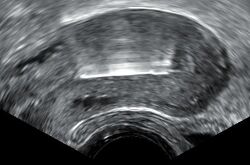

Transvaginal ultrasonography visualizing an IUD with copper in the optimal location within the uterus.